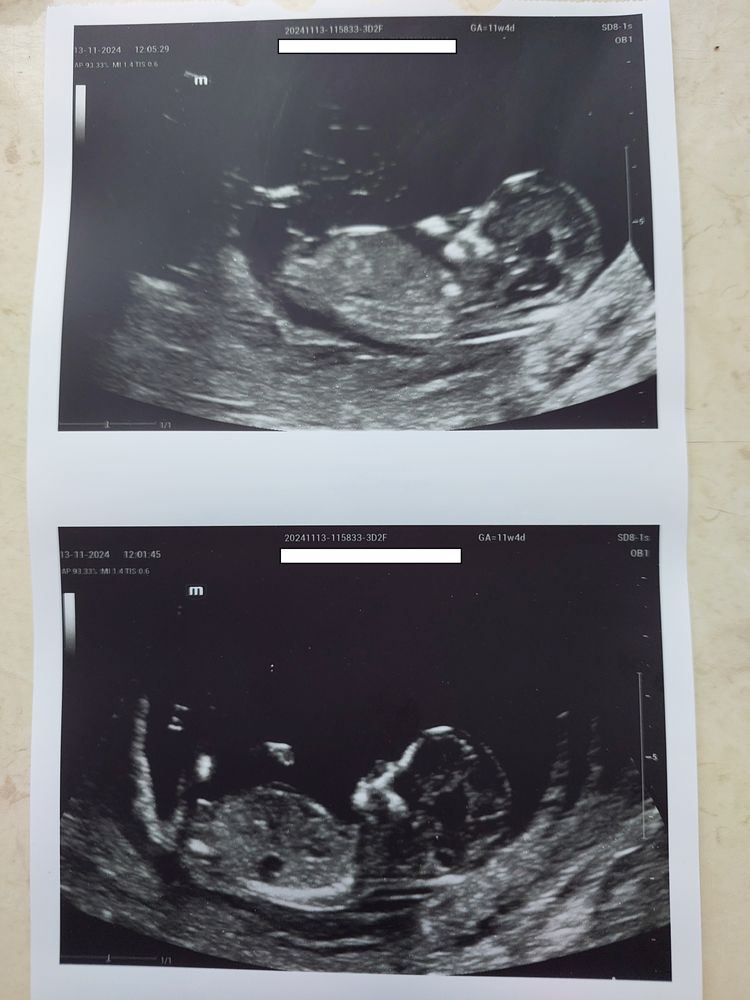

Пол малышаДобрый день всем мамочкам! Беременность 11 нед 6 дн по месячным и 12 нед 5 дн по КТР. Позавчера был первый скрининг в перинатальном центре, через минуту от начала врач спросила: "Пол сказать?", я честно говоря удивилась, но ответила да)) Она сказала 90% что мальчик и показала мне очертания пениса))) Теперь хотим для старшего сына сделать гендер пати, он пока еще не знает о грядущем пополнении в семье, вот хочу сообщить и сразу разрезать тортик) Как думаете можно ли доверять первому скринингу? Здесь читала, что если видят мальчика, то это фактически 100%, а с девочками еще бывают ошибки. Старший сын уж очень хотел братика, хочется его обрадовать)